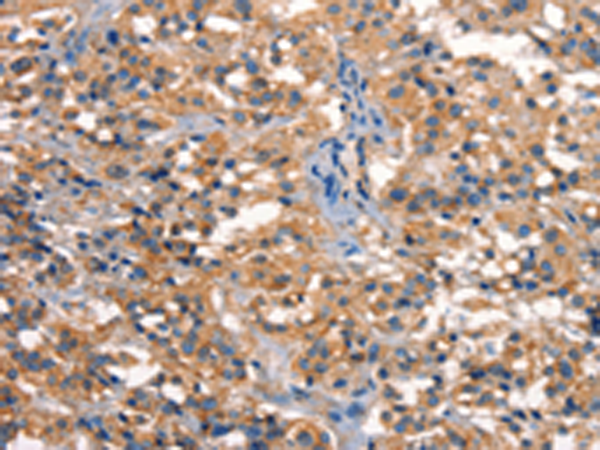

分类: 科研抗体货号: P11213别名: KPM应用: IHC反应种属: Human, Mouse